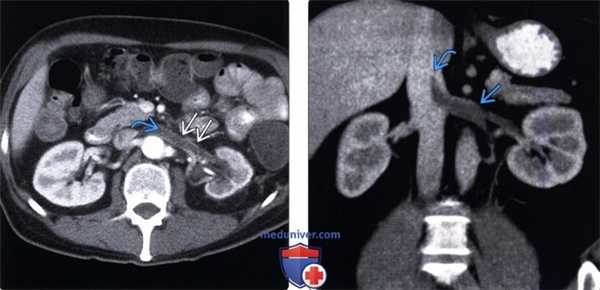

(Левый) У этого пациента имеется хроническая обструкция почки (выполнено стентирование) и инфекционный процесс вследствие опухоли мочевого пузыря. На аксиальном КТ срезе с контрастированием визуализируется цилиндрический низкоинтенсивный дефект наполнения в левой почечной вене, практически с отсутствующим кровотоком по периферии тромба.

(Правый) На фронтальном реформатированном КТ срезе у другого пациента с нефротическим синдромом визуализируется распространенный тромбоз левой почечной вены с переходом на НПВ. Этот пациент впоследствии перенес тромбоэмболию мелких ветвей легочной артерии.